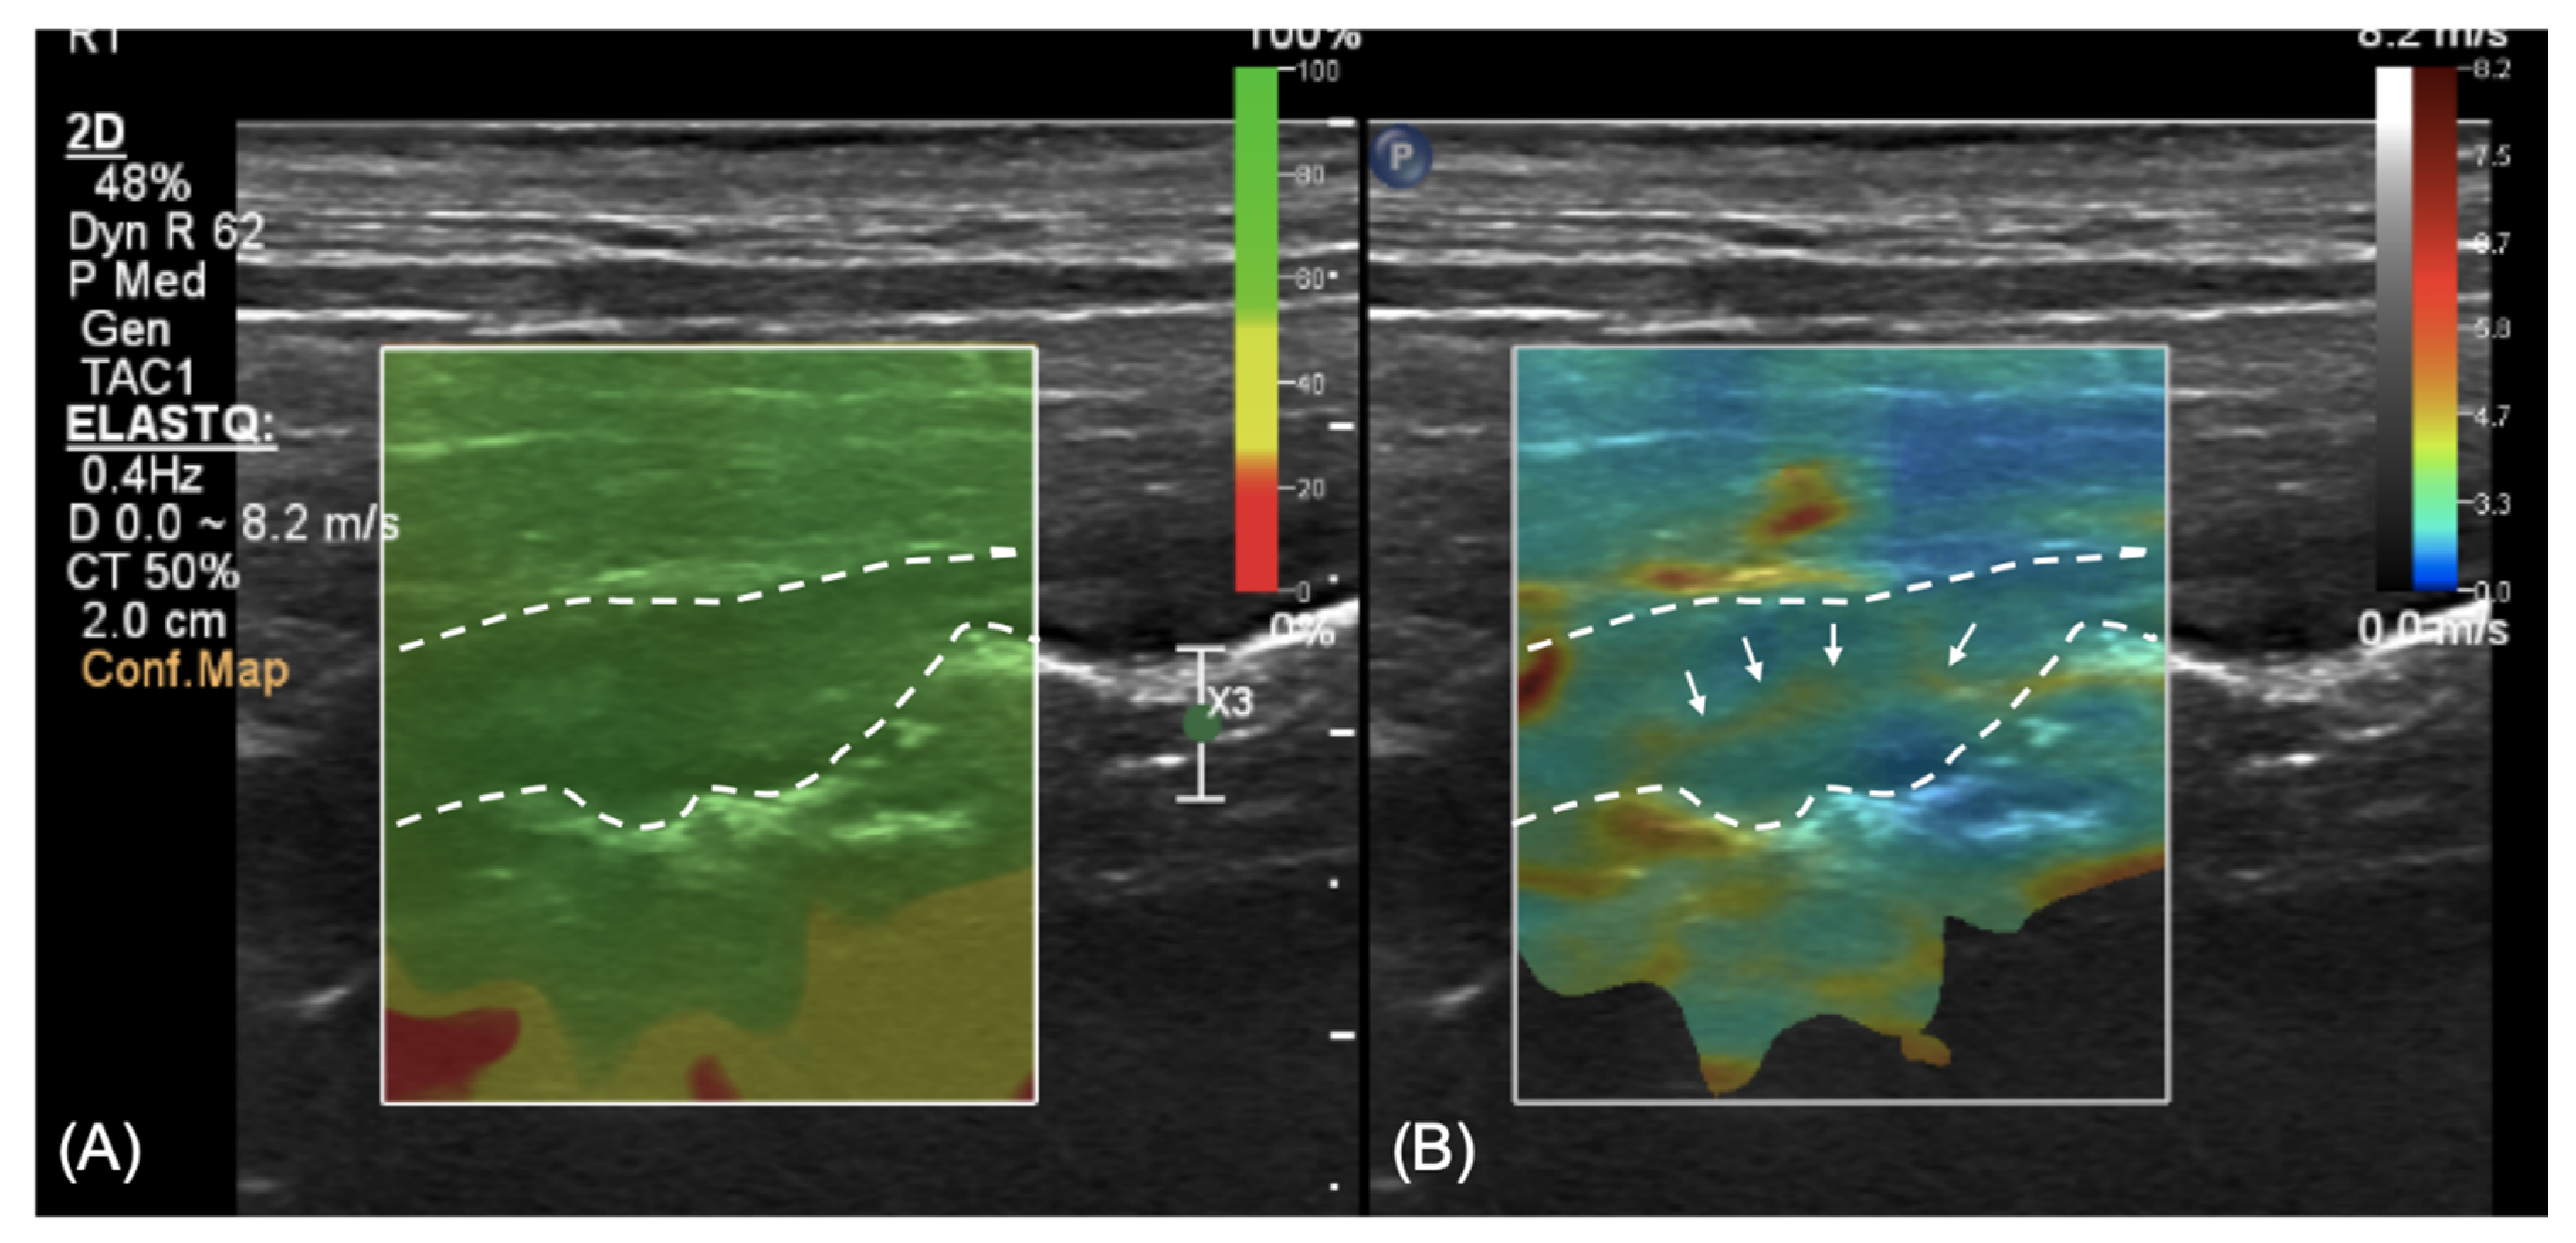

2.2. Imaging Diagnosis